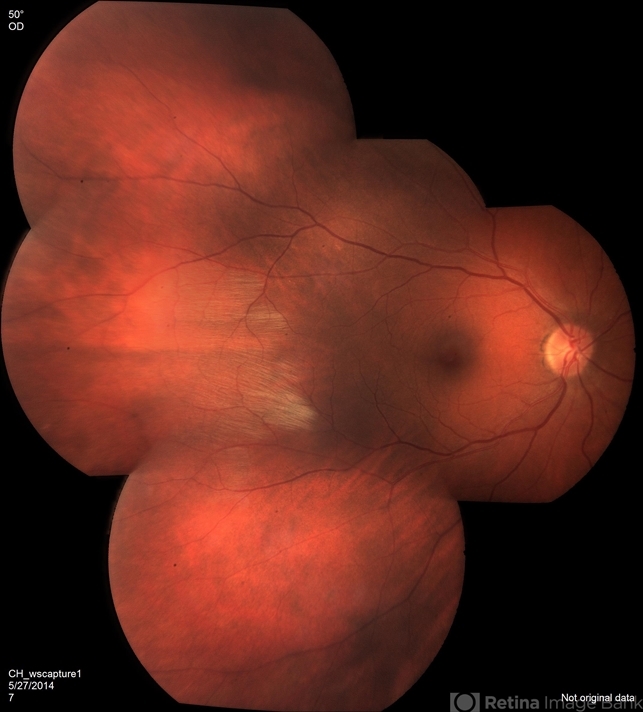

- myelinated nerve fiber layer

- Imaging device

- Fundus camera

- Description

- Myelinated nerve fiber layer.